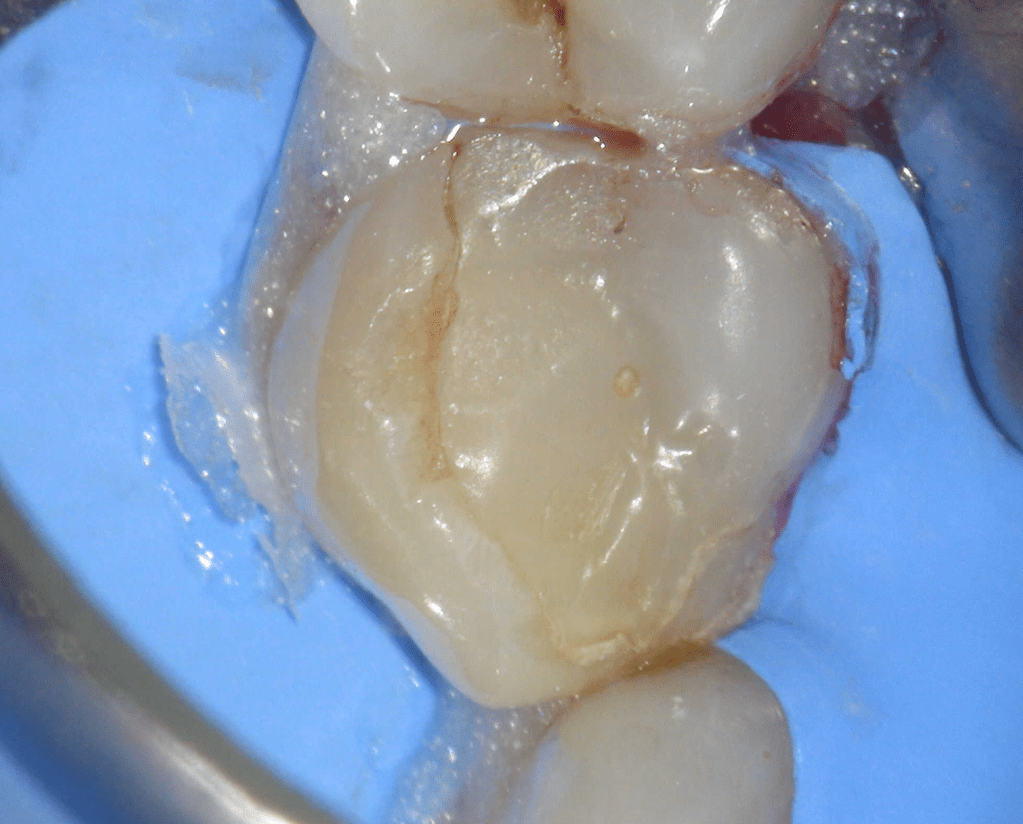

Reco pared vesticular